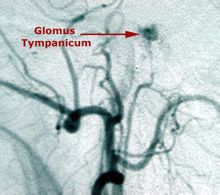

CT檢查對中樞神經系統疾病的診斷價值較高,套用普遍。對顱內腫瘤、膿腫與肉芽腫、寄生蟲病、外傷性血腫與腦損傷、腦梗塞與腦出血以及椎管內腫瘤與椎間盤脫出等病診斷效果好,診斷較為可靠。因此,腦的X線造影除腦血管造影仍用以診斷顱內動脈瘤、血管發育異常和腦血管閉塞以及了解腦瘤的供血動脈以外,其他如氣腦、腦室造影等均已少用。螺鏇CT掃描,可以獲得比較精細和清晰的血管重建圖像,即CTA,而且可以做到三維實時顯示,有希望取代常規的腦血管造影。